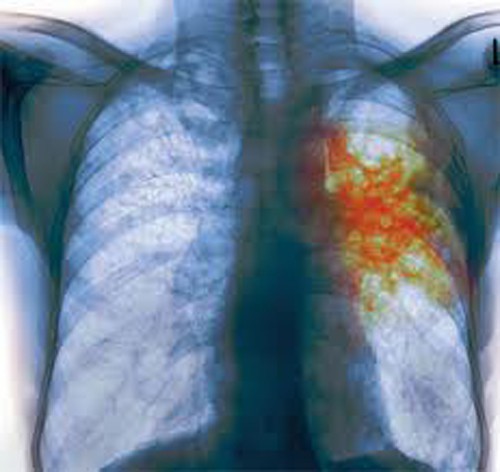

Туберкулез легких – инфекционный процесс развивается непосредственно в легких человека. Данная форма является наиболее распространенной в современном обществе, поскольку возбудители легко передаются здоровым людям воздушно-капельным путем. Отметим также, что с током крови и лимфы палочки могут проникать в другие органы и системы.

Поскольку наиболее распространенной на сегодняшний день формой инфекции является туберкулез легких (диагностируется в 60-70% случаев), мы подробно рассмотрим симптомы туберкулеза именно этой разновидности, тем более что они характерны и для других типов болезни. Итак, у больных наблюдаются следующие признаки туберкулеза:

Специфическая профилактика туберкулеза основывается на вакцинации населения и регулярных флюорографических обследованиях. Последние позволяют вовремя выявить туберкулез легких и начать лечение на ранних стадиях, что снижает вероятность летального исхода. Более частые обследования применяются в отношении лиц, постоянно контактирующих с больными людьми.

Диагностика туберкулеза обычно включает в себя кожный тест на туберкулин, анализ крови, рентгенографию грудной клетки и микробиологическое исследование мокроты. Врач может назначить дополнительные исследования для подтверждения диагноза и определения стадии заболевания.